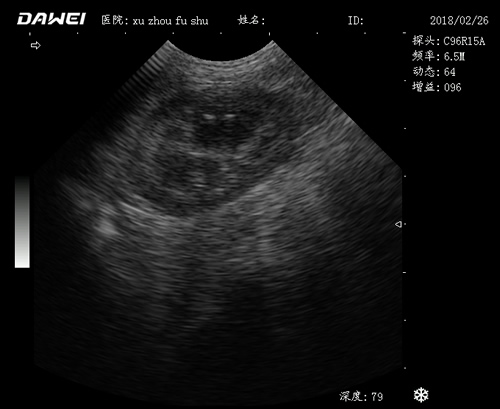

動物寵物超聲診斷儀

·中小動物的肝、膽,脾、腎、膀胱、子宮、妊娠等各組織器官的檢查和病變的診斷